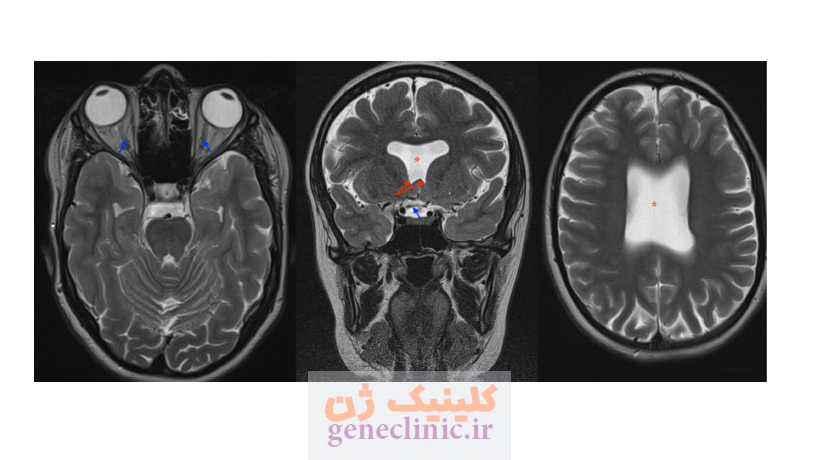

سپتوم پلوسیدوم (septum pellucidum) یک صفحه نازک از بافت عصبی است که دو نیمکره چپ و راست مغز را از هم جدا میکند. در برخی موارد این ساختار وجود ندارد یا به طور کامل تشکیل نشده است. این ناهنجاری در برخی موارد در همراهی با عدم تکامل عصب بینایی (Optic Nerve Hypoplasia) و اختلال عملکرد غده هیپوفیز (Pituitary Gland Dysfunction) دیده می شود که به این وضعیت دیسپلازی سپتو-اپتیک گفته می شود.

- در دیسپلازی سپتو-اپتیک ، علاوه بر عدم وجود سپتوم پلوسیدوم، هیپوپلازی اعصاب بینایی و / یا ناهنجاری های هیپوتالاموس-هیپوفیز وجود دارد.

- MRI مغز جنین برای ارزیابی اعصاب بینایی و chiasm ی بینایی, غده هیپوتالاموس-هیپوفیز و بررسی ناهنجاری های احتمالی در قشر مغز.